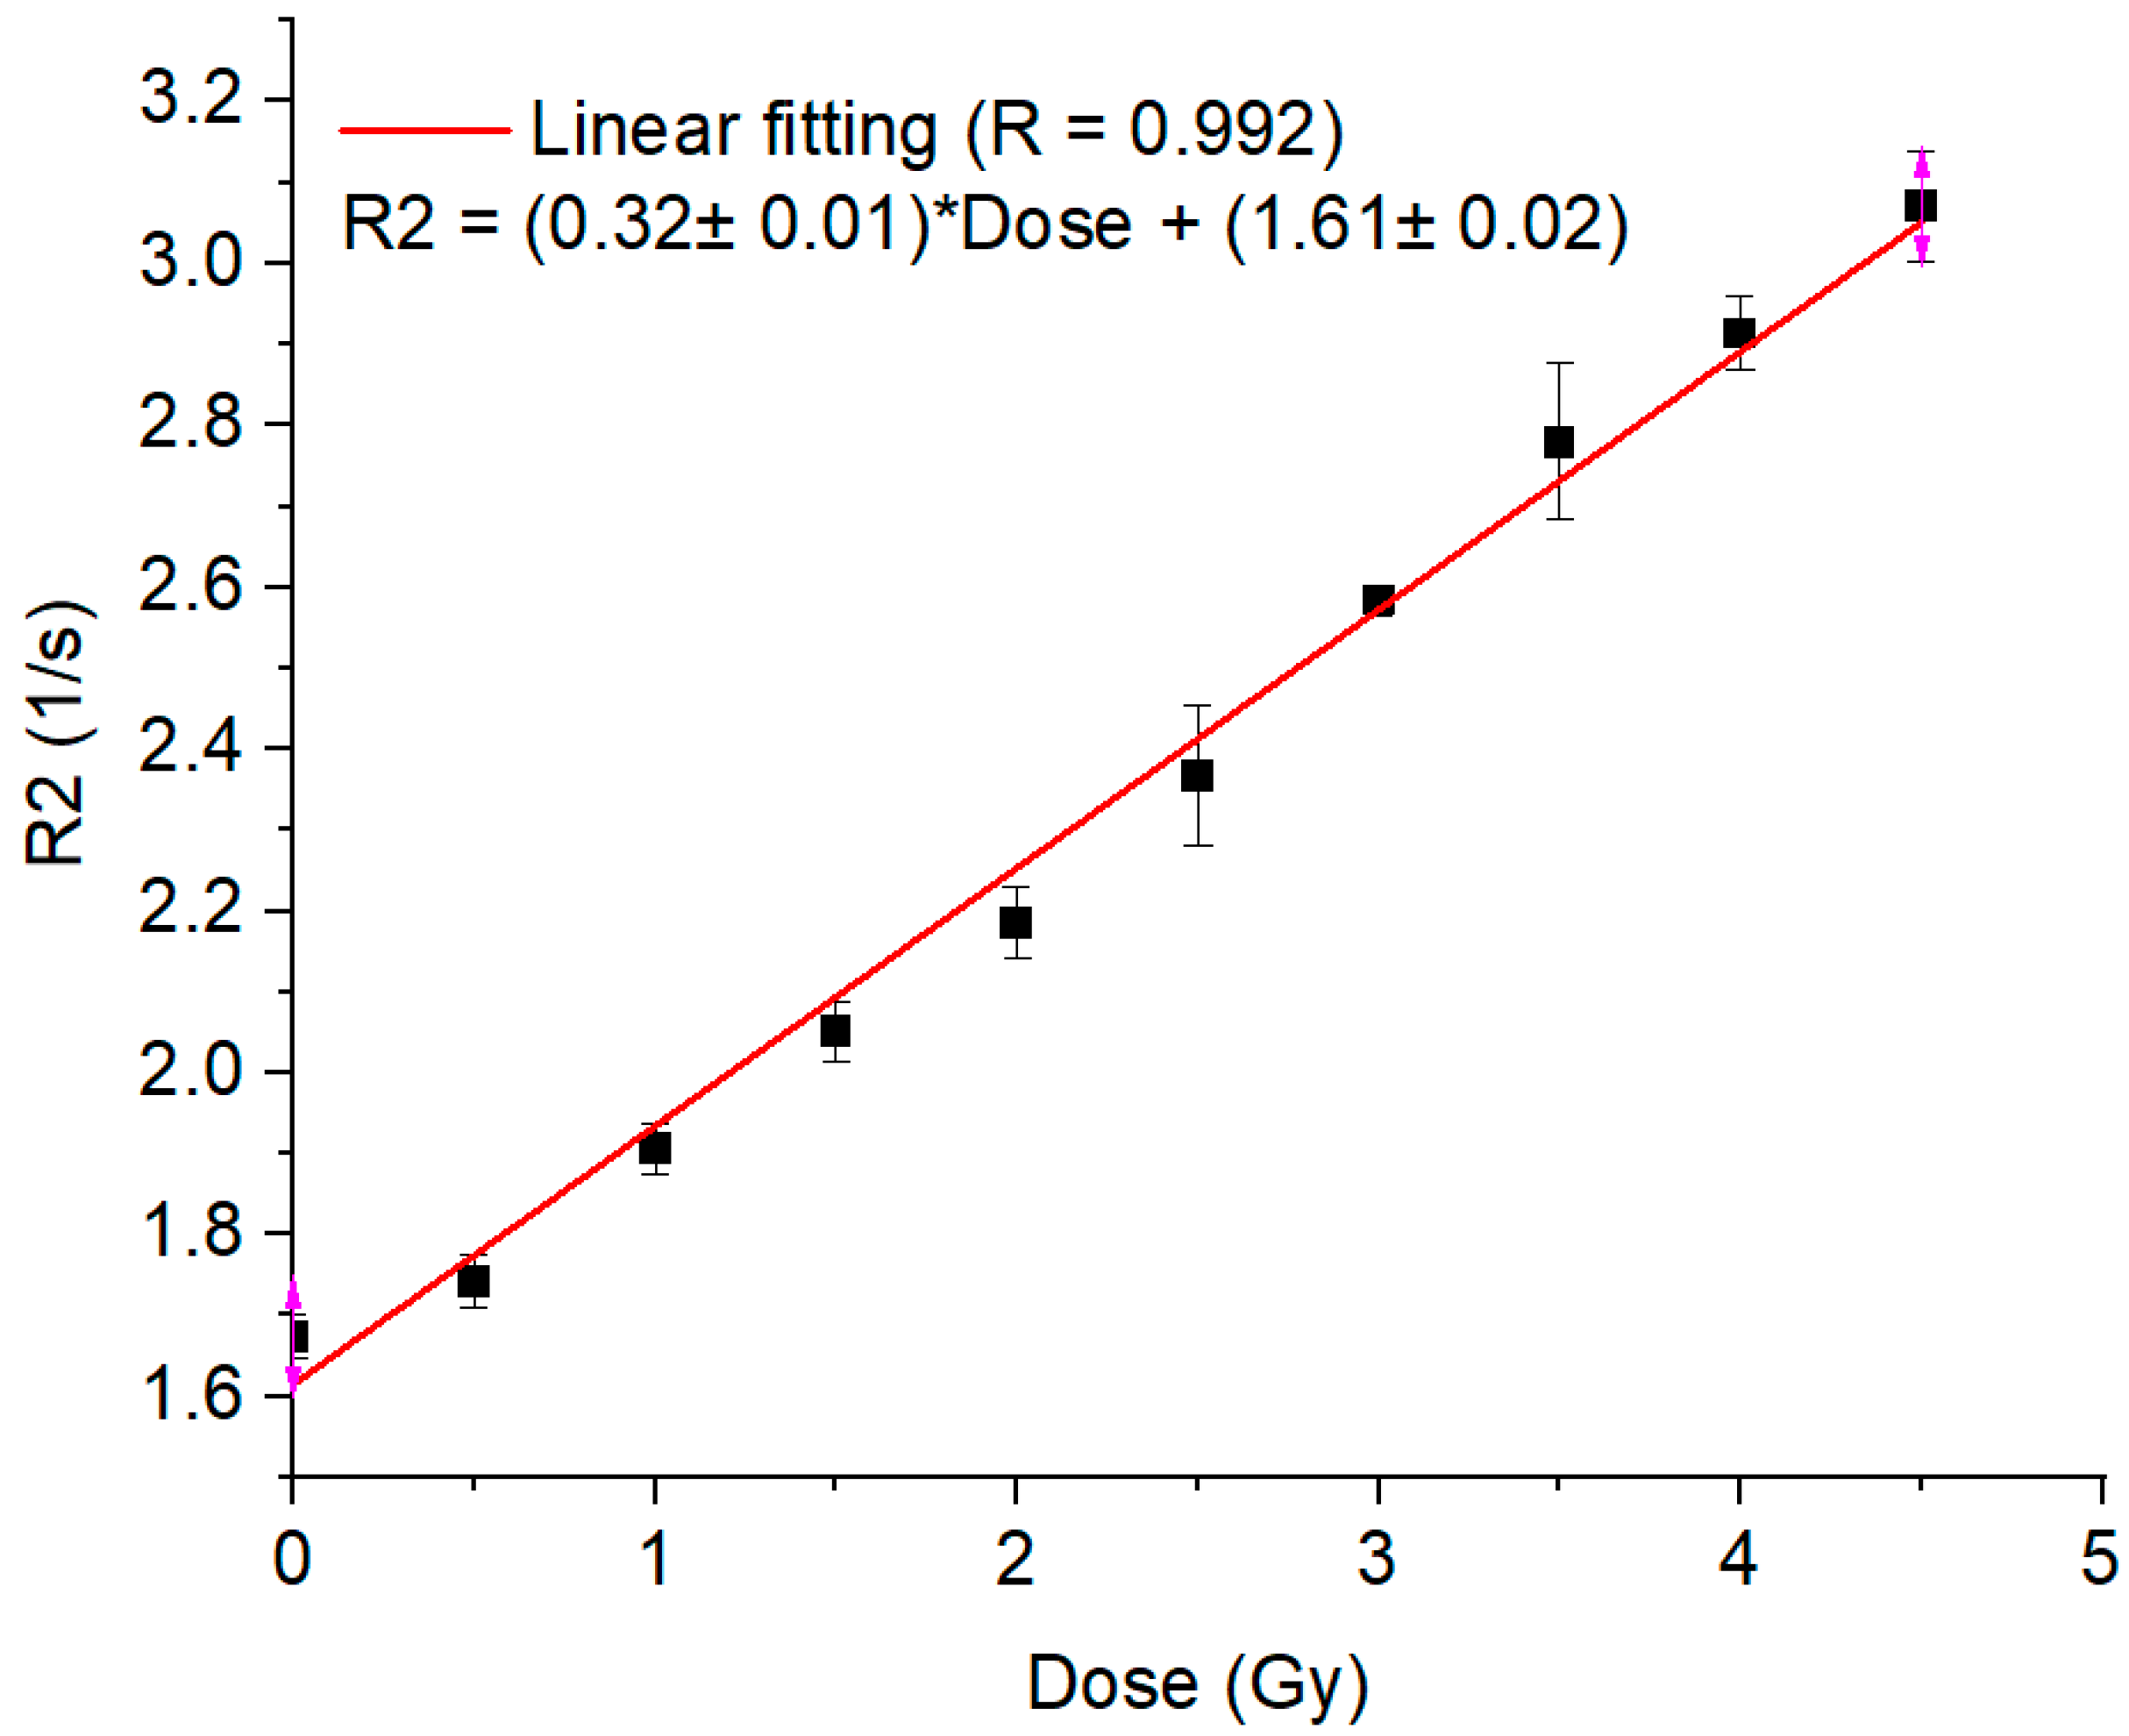

2. Results and Discussion

4. Materials and Methods